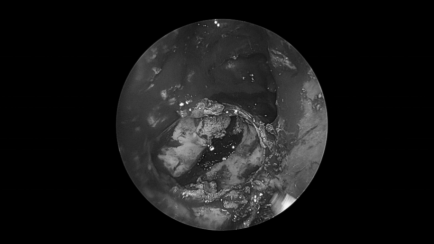

耳内镜检查:分泌性中耳炎(右)

电子喉镜检查:鼻息肉(双)

双耳鼓膜完整,右侧鼓膜内陷明显,右侧鼓室可见积液